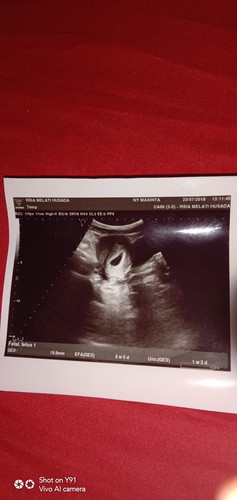

Hasil USG

Ini penjelasannya gimana yaa? Tolong infonya bunda* yg tau

Ges gestational sac alias kantong gestasi. Dari ukurannya didapatkan efa estimated fetal age yaitu 5 mgg 5 hr

5weeks 5days. itu masih kantong kehamilan. di melhus malang kah bund? sm dokter siapa?

Usia kandungannya baru 5 week 5 day bun.. Baru kelihatan kantungnya saja

Baru keliatan kantong, Mungkin 2 mggu lagi keliatan embrionya